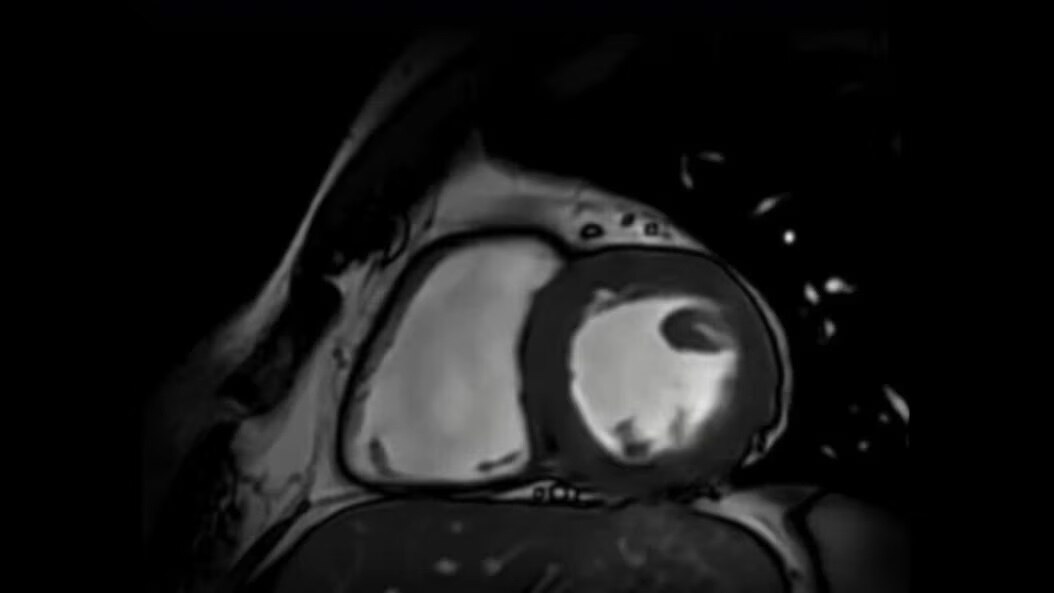

Cardiovascular Imaging for SIGNA

Explore cardiovascular imaging for SIGNA. Assess morphology, flow, and tissue viability with precision. Experience accelerated diagnostics and crystal-clear cardiac MR images with Sonic DL™ technology.